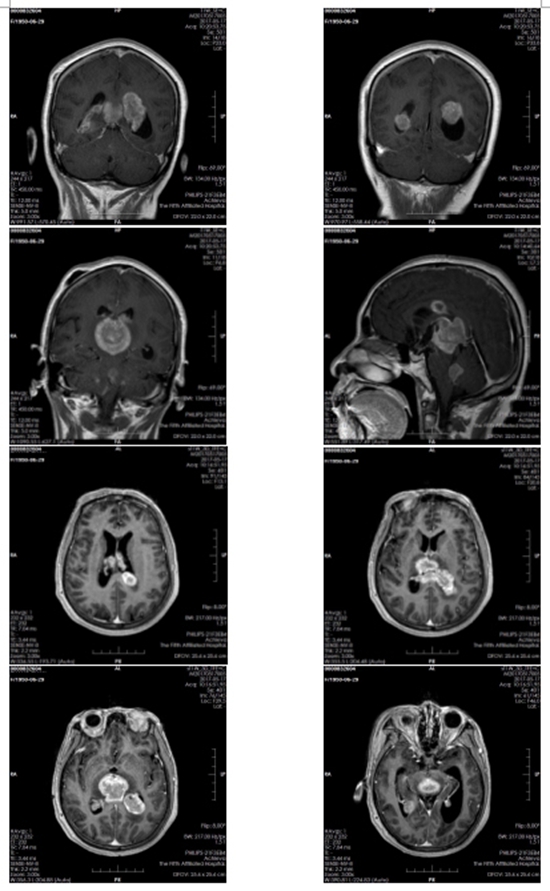

患者放疗后核磁共振图

回到放疗科后,王晓瑜主任迅速成立了以放射治疗医师、物理师、技师组成的治疗团队,对王大妈的病情进行深入的研究和探讨,制定了先行颅内肿瘤精准放疗,待生命体征稳定后再行全脊髓放疗的治疗方案,给予病人抢救性治疗。开通绿色通道,安排优先治疗。王大妈的主管医师任振泰介绍:容积弧形调强放射治疗(VMAT)作为肿瘤治疗疗效好、周围正常组织损伤小的精准放射治疗技术很适合病人此阶段治疗。经过2周放射治疗后,病人意识逐渐恢复。3周复查头部核磁共振成像检查(MRI)提示肿块明显缩小。